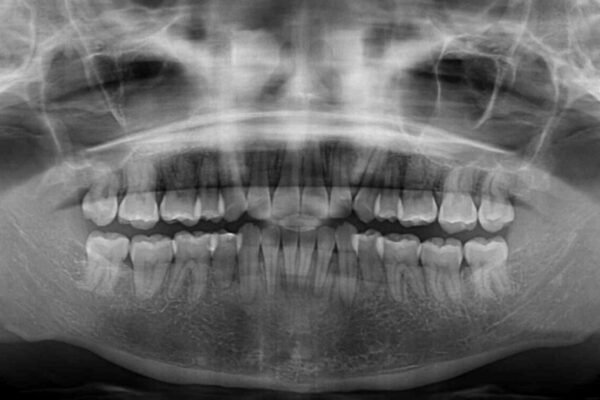

治療計画

上下顎ともに前突した歯列であったので、上下ともに左右の第1小臼歯4本を抜歯し、ワイヤー装置にて矯正治療を行うこととしました。